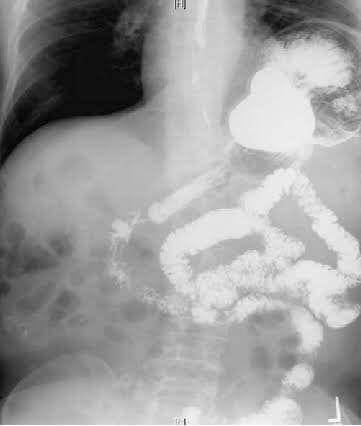

A beautiful case: Left sided Bochdalek Hernia

51 yr old patient with recurrent vomiting and dyspepsia and left sided chest pain. CT, Barium showed fundus and body of stomach in thoracic cavity with Mesentroaxial Volvulus. (image 1-4) Pre-OP thought to be a large sliding paraesophageal hernia operative findings revealed a posterior defect separate from hiatus suggestive of Bochdalek diaphragmatic hernia with a small hiatal hernia. Repair of Bochdalek defect with Crural repair was performed with mesh reinforcement. A 270 degree fundoplication was added (instead of a 360 as Manometry could not be performed preoperatively) (image 6-10) postoperative recovery was smooth (preop-postop xrays image 11-12).